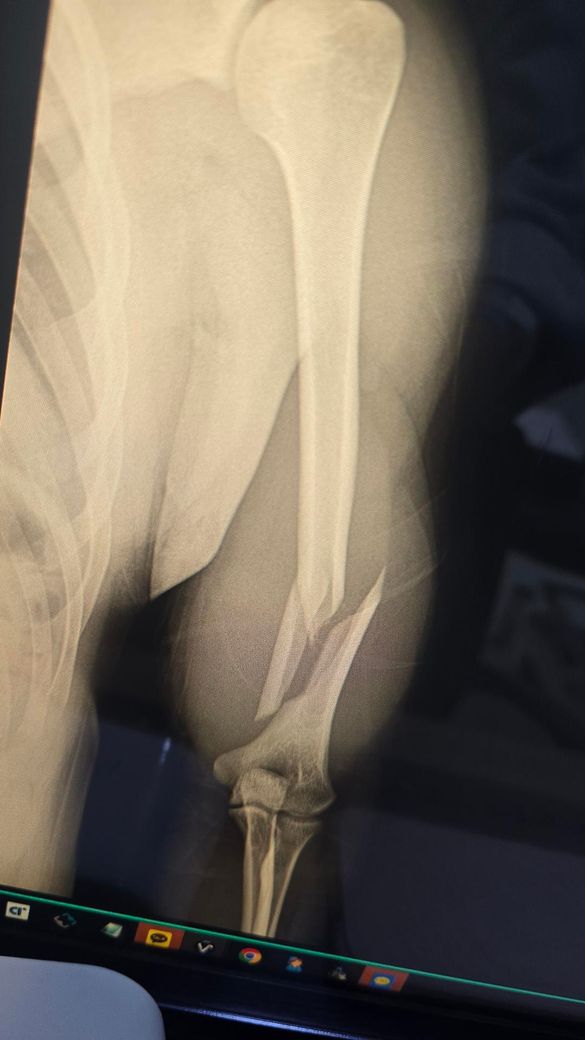

현재 골절 수술후 106일차에요.. 8도정도 틀어졌고 정복이 잘 안됐다고 하는데 아직은 기다려볼 단계일까요 진료는 여러군데 더 예약해놨어요.. 수술부위는 좌우 움직일 때 뼈소리 자주나요

엑스레이상 상완골 원위부의 분쇄골절로 인해 정복이 완벽하지 않고, 금속판 주위로 일부 각변형이 관찰되는 상태입니다.

수술 후 100일이 넘은 시점에서 골절선이 여전히 뚜렷하게 보이며 빈 공간을 채우는 뚜렷한 골진형성이 다소 더뎌 보여 부정유합이나 불유합의 가능성을 염두에 두어야 하는 시기인것은 맞습니다. 다만 부정유합은 뼈가 아예 붙지 않는것이 아니라 잘못된 모양으로 붙는것을 의미하며, 현재의 각도가 기능에 큰 지장을 주지 않는다면 무조건적인 재수술보다는 경과를 더 지켜볼수도 있습니다. 움직일때 나는 소리는 골절부위의 미세한 움직이미 때문일수 있으므로 절대적인 안정과 추가적인 고정이 필요할수 있습니다. 예약된 진료를 통해 골유합진행 여부를 면밀히 확인하시길 권합니다. 빠른쾌유를 빕니다!

• 제시된 영상은 상완골 간부 골절에 대해 금속판 고정술 시행 후 약 3개월 경과한 상태로 보이며, 골절 부위의 정렬은 유지되고 있으나 피질 연속성이 완전히 회복되었다고 보기는 어렵고 가교성 골진 형성도 충분히 성숙한 형태로 뚜렷하게 보이지는 않습니다. 초기 전위가 있었고 현재 약 8도 정도의 각형성이 남아 있는 점을 고려하면, 현재 단계에서 가장 우선적으로 의심되는 것은 부정유합이라기보다는 지연유합입니다.

상완골 간부 골절은 다른 장관골에 비해 유합이 늦는 경우가 흔하며, 수술 후 3개월 시점에서는 유합이 진행 중일 수 있는 시기입니다. 다만 이 시기에 골진 형성이 부족하거나 골절선이 여전히 명확하게 남아 있다면 향후 유합 지연 또는 불유합으로 진행할 가능성이 있어 주의가 필요합니다. 8도 정도의 각형성은 기능적으로 허용 범위에 속하는 경우가 많으나, 회전 변형이나 통증, 기능 제한이 동반되면 임상적 문제로 이어질 수 있습니다.

움직일 때 느껴지는 소리는 단순 연부조직 마찰일 수도 있으나, 골절 부위의 미세한 움직임이나 고정 안정성 부족을 시사하는 경우도 있어 경과 관찰에서 중요한 단서가 됩니다. 특히 통증이 지속되거나 점차 증가하는 양상이면 유합 지연 또는 고정 실패 가능성을 더 신중하게 봐야 합니다.

현재 시점에서는 즉시 재수술을 결정하기보다는 유합 진행 여부를 객관적으로 평가하는 것이 중요하며, 단순 방사선 외에 CT를 통해 골절면의 실제 연결 여부를 확인하는 것이 도움이 됩니다. 일반적으로 수술 후 3개월에서 6개월 사이에 유합이 진행되지 않거나 정체되는 경우, 또는 통증과 기능 저하가 지속되는 경우에 재수술을 고려하게 되므로, 현재는 다기관 진료를 통한 2차 의견과 함께 일정 기간 추적 관찰을 병행하는 접근이 타당한 단계로 판단됩니다.